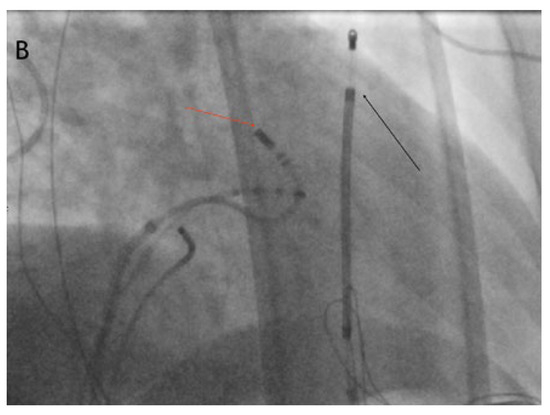

Direct His bundle pacing has recently attracted interest as a more physiological alternative to right ventricular or biventricular stimulation. The advent of new tools has facilitated the implantation procedure. This report relates our initial experi...